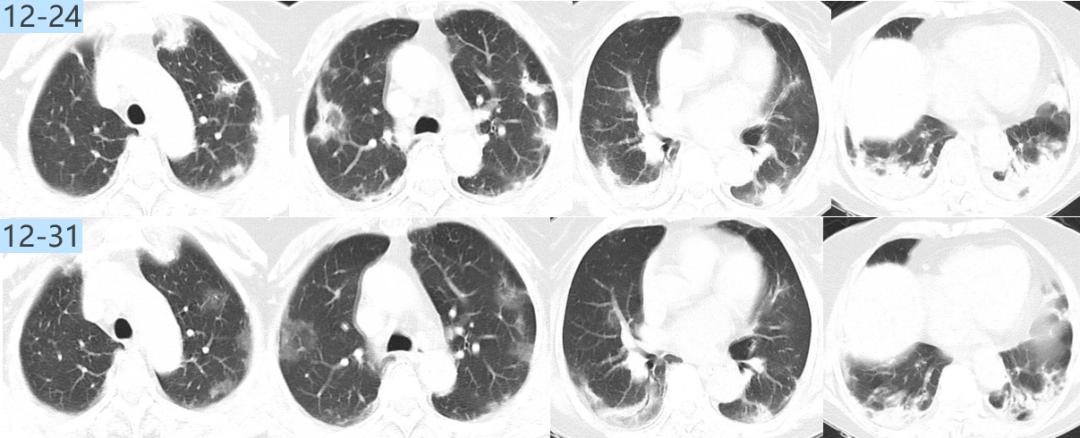

治疗中患者的氧合指数仍然在快速下降,我们复查CT,显示大部分病变在进展。

图:胸部CT(12-24):两肺纹理增多,两肺门影增浓,两肺野内多发斑片影,较前2021-12-18部分稍有好转,部分稍明显。

仔细比对后,我发现有一个病灶吸收了,机化性肺炎?气管镜下并没有明显感染的征象,后来,NGS只检出纹带棒状杆菌7个序列、光滑念珠菌16个序列,载量很低,而且这两个病原体本身就存在于呼吸道,所以我将它们定义为阴性。

这时进行治疗调整:2021.12.24-12.26:比阿培南0.3g q6h+替加环素 100mg q12h+甲强龙 120mg qd;12.27-2022.01.02:哌拉西林他唑巴坦4.5g q6h+甲强龙 40 mg qd。激素加量、抗生素两天后减量了。治疗效果体现在氧合指数上,患者的氧合指数开始抬头。经过7天的治疗,CT显示所有病灶都在吸收。

图:胸部CT(12-31):两肺野内多发斑片影,较前好转。

修正诊断患者为机化性肺炎,携带激素出院。只要缓慢减量、疗程足够长,大部分患者不会反弹